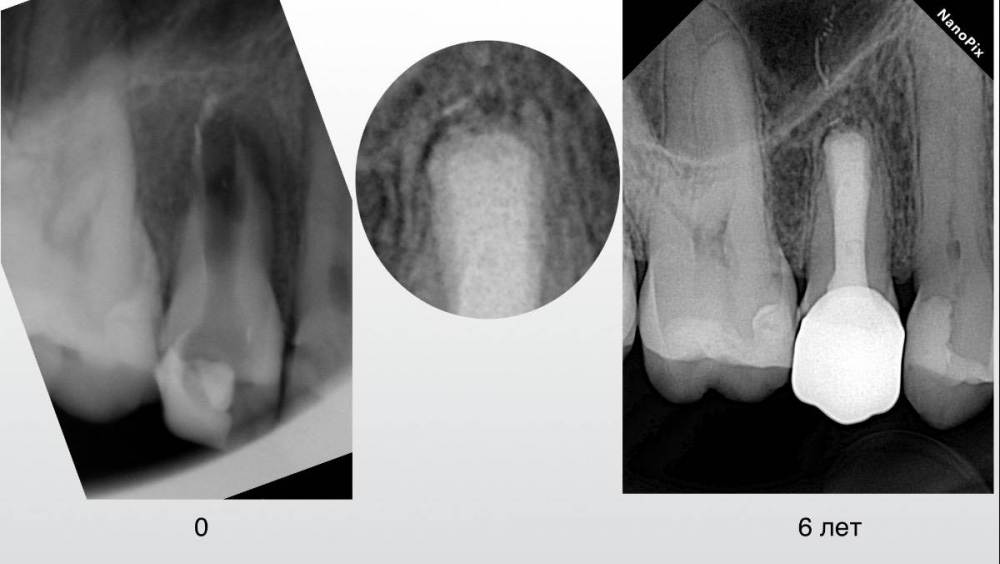

Гарриевич Опубликовано 2 августа, 2018 Автор Поделиться Опубликовано 2 августа, 2018 Вот вся история в картинках 13 Ссылка на комментарий

ger_berra Опубликовано 9 августа, 2018 Поделиться Опубликовано 9 августа, 2018 Вот вся история в картинкахF3CD8F8E-36A2-482B-BFD4-6A0883546283.jpeg2A06B29D-2BDF-4869-A8F8-E02567619146.jpeg47F31C36-F9FE-40C6-9236-3A6203A894B7.jpeg8459AB75-F819-4664-9906-DB4BDCE505D2.jpeg9937DA00-9922-402C-AA29-5DD806AA0714.jpeg37DDB315-6893-49F4-A949-06BC6B58F996.jpegОтличный результат! 1 Ссылка на комментарий

Гарриевич Опубликовано 22 апреля, 2022 Автор Поделиться Опубликовано 22 апреля, 2022 (изменено) 2020 год. Прошло 4 Года. Скоро посмотрим реколл 6 лет:) Изменено 22 апреля, 2022 пользователем Гарриевич 5 1 Ссылка на комментарий

Гарриевич Опубликовано 27 марта, 2023 Автор Поделиться Опубликовано 27 марта, 2023 6 лет прошло 3 1 2 Ссылка на комментарий